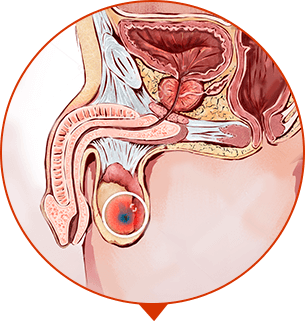

PROSTAT ADENOMASI

Prostat dokusunun büyümesi, tümör ve 'kütle' oluşumu

-

KANSER

Erkeklerde en yaygın ölüm nedeni olarak görülen kanserli tümör